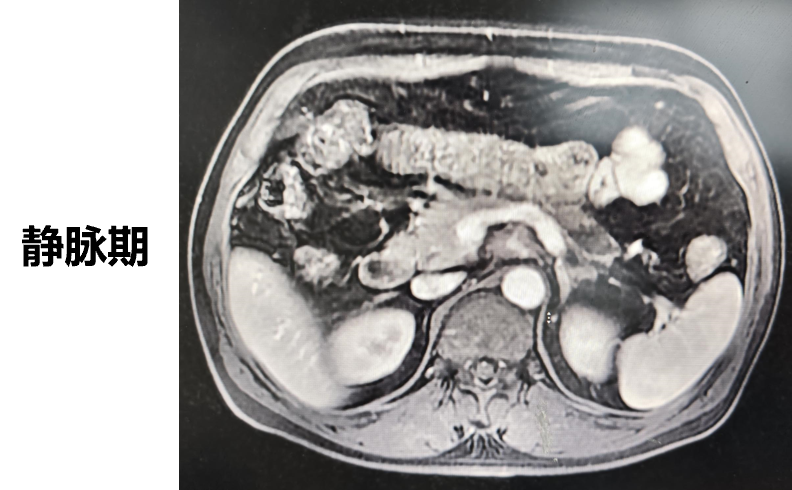

◈ 2023-3-9 上腹部MR增强扫描,对比2023-1-19上腹部MR:胰周多发囊性病变,考虑为术后改变(活检后),假性囊肿形成可能,较前吸收缩小;肠系膜上动脉、腹腔干近段及局部分支周围软组织影,较前缩小,研究者评估整体疗效为部分缓解(PR)。

2023-3-9上腹部MR增强扫描—TTFields联合化疗治疗五月余